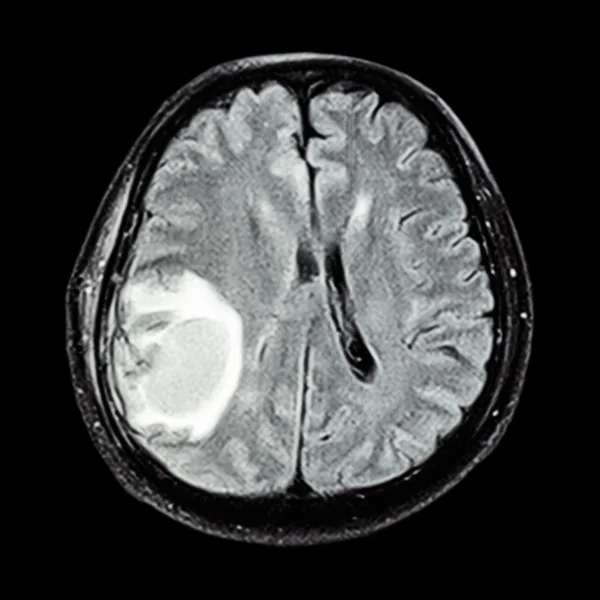

Brain cancer, MRI scan Stock Image M134/0469 Science Photo Library

Brain cancer, MRI scan Stock Image M134/0469 Science Photo Library Does Blood Work Show Brain Cancer brain cancer can cause a variety of neurological symptoms, as well as systemic (whole body) effects. brain tumours can affect people of any age, including children, although they tend to be more common in older adults. Brain cancer may develop gradually,. A biopsy is a major procedure, and it is the most definitive test for brain tumor diagnosis.. Does Blood Work Show Brain Cancer.